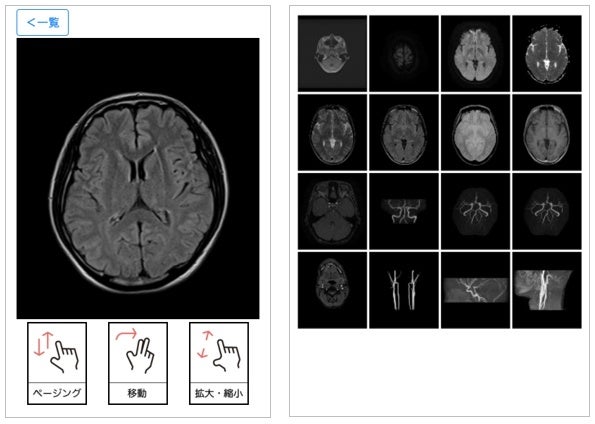

メールに記載されている「検査画面を確認する」またはマイページの検査結果レポートから「すべての撮影画像を見る」を選択するとビュアーが立ち上がり、画像を確認することができます。

また、画面を上下にスライドすると、複数枚の連続画像がご覧いただけます。

結果画像サンプル

「スマート脳ドック」は、脳動脈瘤や脳梗塞、脳腫瘍などの自覚症状のない脳の異常を早期発見できる頭部MRIおよび頭部・頸部MRAの検査です。